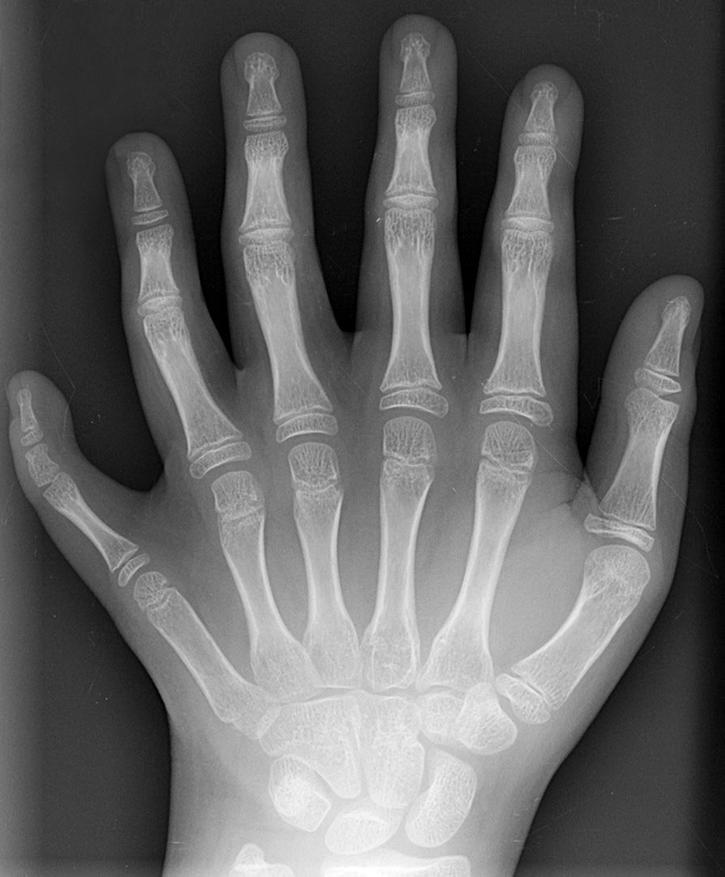

Пятипалая структура (в науке это называется пентадактилией) оказалась настолько устойчивой, что сохранилась даже у тех животных, которым пальцы, казалось бы, уже не нужны. Это явление демонстрирует принцип гомологии — сходства органов, имеющих общее происхождение, но выполняющих разные функции.

Если рассмотреть скелет грудного плавника кита, дельфина или морского льва, мы увидим те же кости плеча, предплечья и, что самое удивительное, пять пальцеобразных лучей, скрытых под толстым слоем кожи и жира. Животные вернулись в воду миллионы лет назад, но их скелет сохранил память о сухопутном прошлом.

То же самое касается рукокрылых. Крыло летучей мыши — это не новая конечность, а сильно видоизмененная кисть. Тонкая кожаная перепонка натянута на удлиненные фаланги тех же самых пяти пальцев.

Даже у животных, которые в процессе эволюции утратили пальцы, развитие эмбриона начинается с классической схемы. У эмбрионов лошадей или птиц на ранних стадиях формируются зачатки пяти лучей. Лишь позже генетическая программа запускает процесс редукции (отмирания) «лишних» элементов, оставляя один палец (превращающийся в копыто) или три (формирующие крыло).

Редкие случаи рождения людей с шестью пальцами (полидактилия) являются результатом сбоя в работе конкретного гена-регулятора, известного как Sonic hedgehog. Этот ген контролирует ширину конечности и количество элементов в ней. Однако в норме система жестко блокирует такие отклонения, возвращая организм к стандарту «пять».